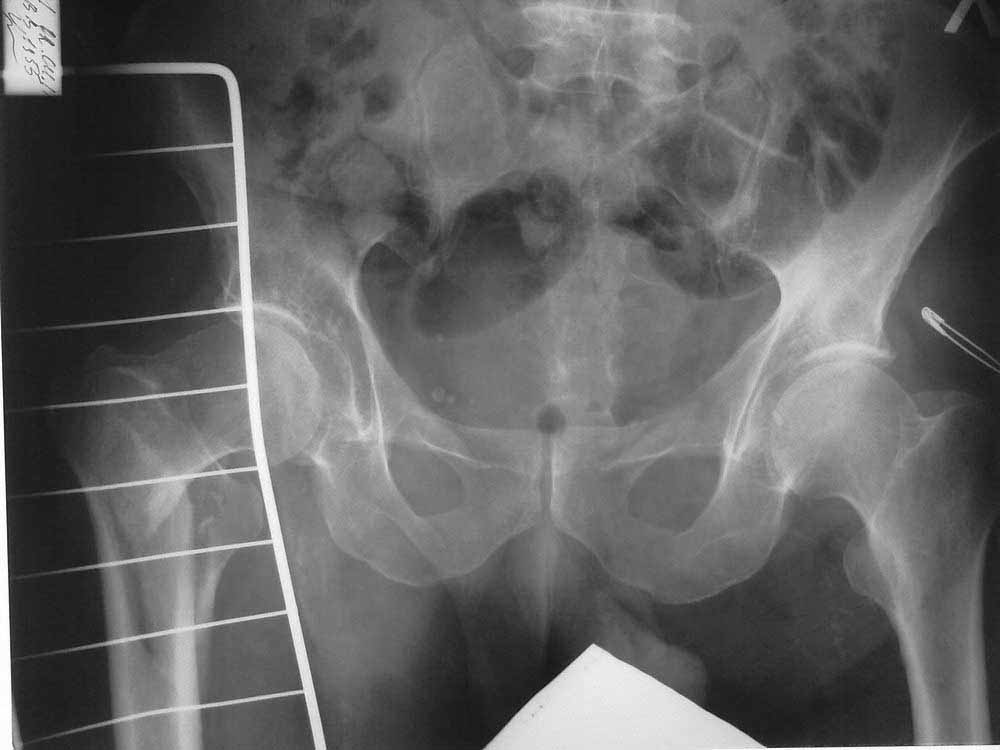

[Ortho] чрезвертельный перелом

Уважаемые коллеги! Подскажите тактику ведения больного с чрезвертельным перелом.

Больной 56 лет. Травма в быту, упал на правое бедро. Доставлен по линии скорой помощи.

Правая нижняя конечность ротированна кнаружи, укорочение на 4 см. Резкая боль в области правого ТБС.

В анамнезе инсульт от 04.2010 г, повторный инсульт 28.02.2011 г. DS:Хроническая дисциркуляторная энцефалопатия II ст., последствия ОНМК в виде выраженного спастического гемипареза справа.

Раньше больной передвигался с опорой на правую нижнюю конечность, но активных движений в ноге не было.

Сейчас на скелетном вытяжении, с грузом 8 кг, за бугристость большеберцовой кости.

Имеет ли смысл делать операцию вообще? Может быть сохраняющую сустав или артродез?